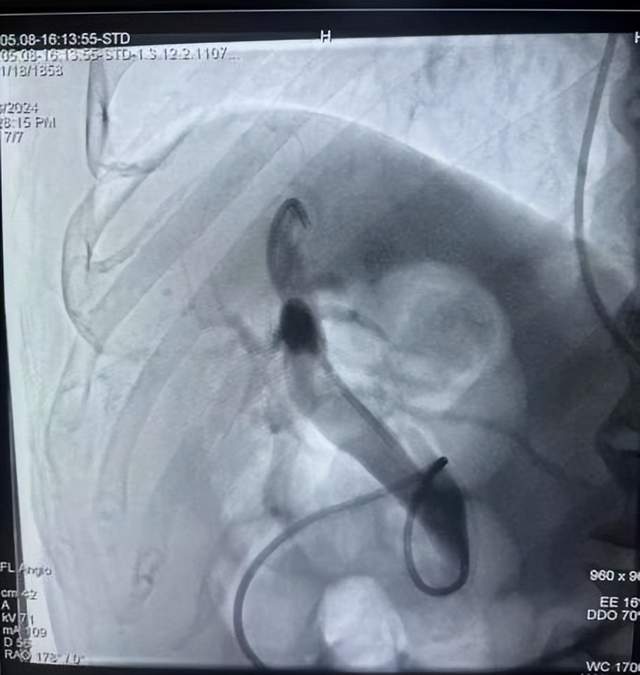

仔细研究患者病情和影像学资料,普外科团队经讨论后,提出最佳治疗方案即行“ERCP+EST取石+腹腔镜下胆囊切除术”。

患者术中图片

5月8日,团队为姚爷爷在全麻下“经内镜逆行胰胆管造影(ERCP)+乳头括约肌切开术(EST)+胆管球囊扩张+取石+鼻胆管引流术(ENBD)+腹腔镜下胆囊切除(LC)”综合手术。术中,因患者有胃穿孔手术史,造成十二指肠球部、胃窦部与肝脏粘连严重,给十二指肠镜下操作及LC手术切除均造成较大困难。在手术团队的密切配合下,最终姚爷爷安全顺利地完成此次手术。